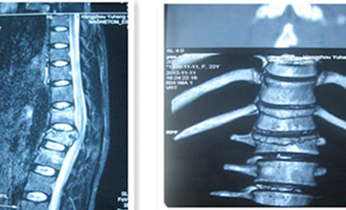

頸、胸、腰椎手術治療

等離子射頻消融髓核成形術